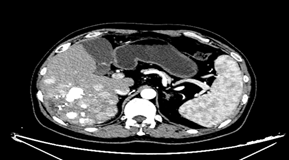

基于mRECIST标准,可判定为一线治疗后疾病进展。遂换用瑞戈非尼联合PD-1单抗治疗。2020年7月6日异常凝血酶原降至49.89 ng/ml。2020年9月17日再次复查,肝增强CT提示,肝脏多发占位性病变,病灶内可见肿瘤存活。病情较前稳定,未见显著进展。

图片

图:肝增强CT(2020-9-17)